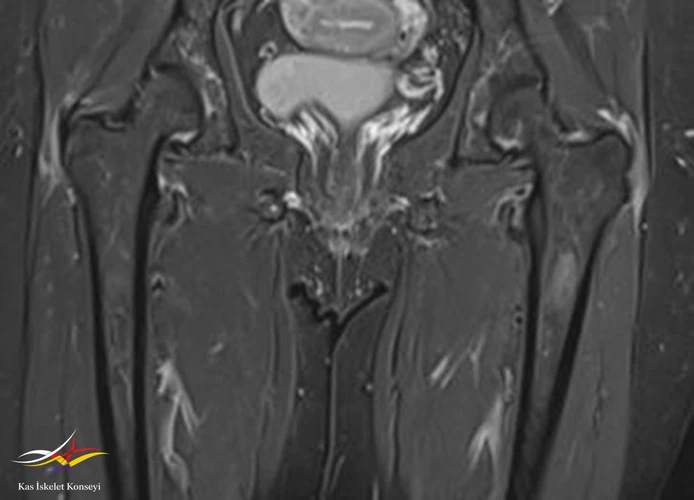

İncelemeler: Lomber MRG: L4-5 diskal bulging ve sol foraminal stenoz var. Kalça MRG istendi, iki yanlı trokanterik bursit rapor edildi.

Resim 4. Kalça MRG koronal kesit, solda hakim iki yanlı trokanterik bursit ile uyumlu.

Tedavi için öncelikle trokanterik bursa enjeksiyonları öngörüldü. Bu tedaviden alınacak yanıt görüldükten sonra mevcut lomber patolojisinin (foraminal stenoz) tekrar değerlendirilmesi önerildi. İki yanlı belirgin trokanterik bursit görülmesi nedeniyle polimyalgia romatika açısından da incelenmesi önerildi.